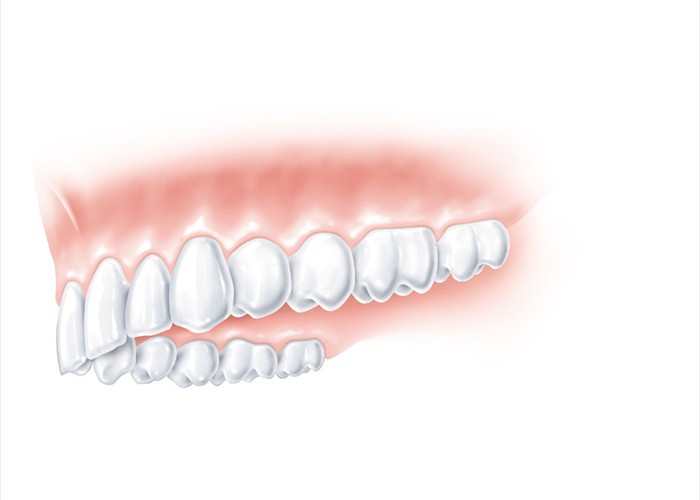

Zahnloser Oberkiefer - bei einer klassischen Versorgung müsste hier eine totale Prothese eingegliedert werden.

Zahnloser Oberkiefer - bei einer klassischen Versorgung müsste hier eine totale Prothese eingegliedert werden.